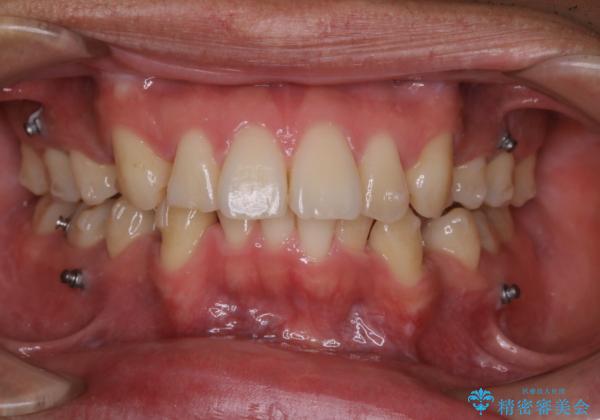

矯正中は汚れが付きやすいため、着色がとても多く付いていました。

抜歯したスペースや装置の周りの磨き方などとても難しため、定期的にクリーニングをおすすめします。